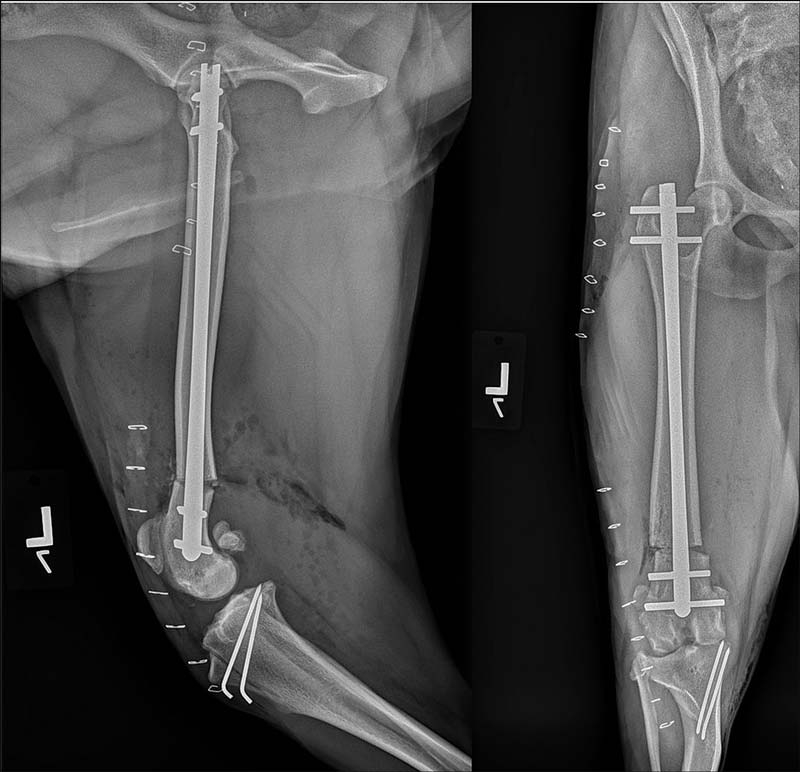

Figure 4. Postoperative mediolateral and caudocranial views of the left femur of the same case as seen in Figures 1 and 2 following an opening osteotomy of the distal femur, stabilised using an interlocking nail and a tibial tuberosity transposition to correct grade III medial patellar luxation.

An alternative, which may facilitate the procedure, is a medial opening wedge osteotomy stabilised using an interlocking nail (Figure 4).